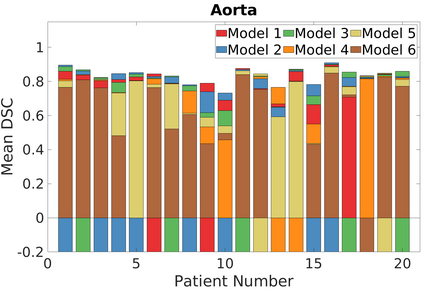

Deep Convolutional Neural Networks (DCNNs) are used extensively in biomedical image segmentation. However, current DCNNs usually use down sampling layers for increasing the receptive field and gaining abstract semantic information. These down sampling layers decrease the spatial dimension of feature maps, which can be detrimental to semantic image segmentation. Atrous convolution is an alternative for the down sampling layer. It increases the receptive field whilst maintains the spatial dimension of feature maps. In this paper, a method for effective atrous rate setting is proposed to achieve the largest and fully-covered receptive field with a minimum number of atrous convolutional layers. Furthermore, different atrous blocks, shortcut connections and normalization methods are explored to select the optimal network structure setting. These lead to a new and full-scale DCNN - Atrous Convolutional Neural Network (ACNN), which incorporates cascaded atrous II-blocks, residual learning and Fine Group Normalization (FGN). Application results of the proposed ACNN to Magnetic Resonance Imaging (MRI) and Computed Tomography (CT) image segmentation demonstrate that the proposed ACNN can achieve comparable segmentation Dice Similarity Coefficients (DSCs) to U-Net, optimized U-Net and hybrid network, but with significantly reduced trainable parameters due to the use of full-scale feature maps and therefore computationally is much more efficient for both the training and inference.